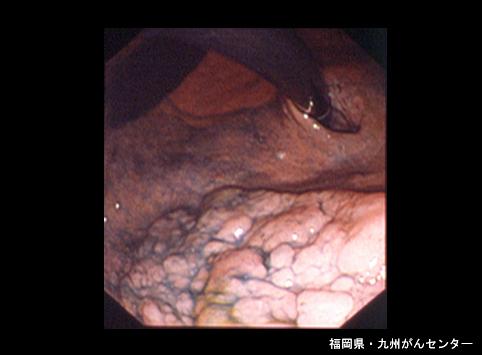

Posted by: Fukuoka Pref., 큐슈암센터

질환(병리주체)의 분류 악성 상피성종양/선암

부위(장기별) 위(부위)/체부

검사방법 내시경

종양의 육안분류 0형(표재형)/IIa형(IIa)

종양의 최대경(밀리미터) 30~34

종양의 심달도 sm